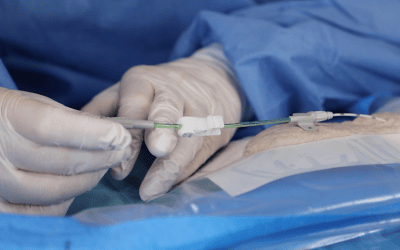

5. Uso del ecógrafo para la punción + Seldinger modificada (imagen 5 A y B):

El ultrasonido aumenta el éxito de punción de la vena al primer intento. Nos permite también tener un control total de la aguja durante la inserción.

Las guías internacionales recomiendan la punción vascular con ecografía y la evidencia ha demostrado que es el modo más seguro y costo-efectivo de realizar la punción. Así mismo, el uso de la técnica de Seldinger modificada (que incluye aguja ecogénica de 21G, pelo en nitinol con punta blanda y microintroductor pelable) permite trabajar en vasos de pequeño calibre como son los del brazo, reduciendo el daño endotelial que pudiera derivarse de la punción venosa e introducción posterior del catéter.